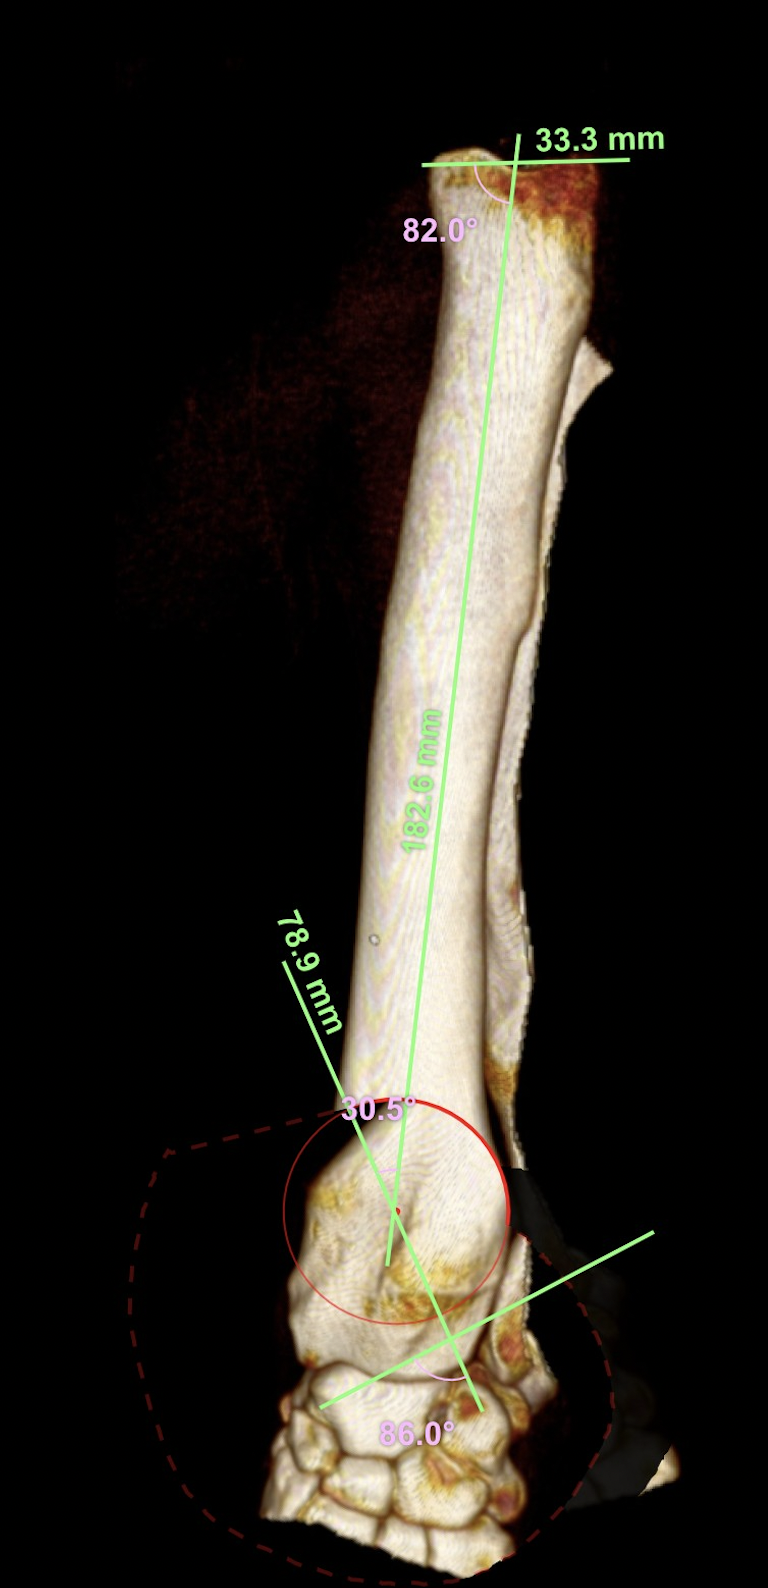

橈骨遠位外反変形に対するPaley’s rule 矯正骨切り術

大型犬の橈骨遠位変形矯正をPaley’s ruleを元に、Center Of Rotation Angulation(変形中心角)を決定し、vPOPでシミュレーションを行い骨切り矯正術を行った。機能軸もしくは解剖軸を骨軸上に配列できなければ2次的な変形が生じてしまうリスクがある。橈骨遠位のCORAを中心にラウンドオステオトミーを実施3.5 Locking PlateでOrthogonal法で整復固定を行う。このテクニックでは骨切除を行わないので脚短縮が生じないというメリットがあります。